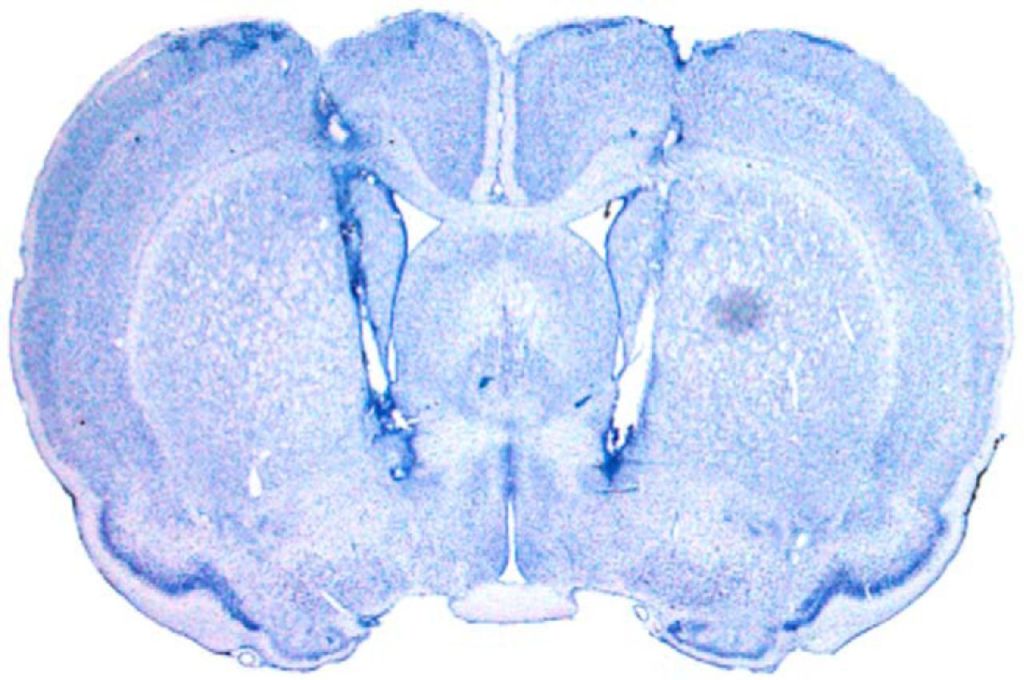

Extinction-based therapies, such as prolonged exposure, are used to reduce fear in patients with fear and anxiety disorders. Unfortunately, the loss of fear that occurs during extinction is often limited to the extinction context and vulnerable to relapse. We are mapping the neural circuits involved in extinction memory and fear relapse. We focus on connections between the hippocampus, amygdala, and prefrontal cortex. A recent focus has been on the role of the nucleus reuniens, which interconnects the hippocampus and medial prefrontal cortex, in extinction acquisition and retrieval. This project is funded by a the NIH (R01MH065961). Recent paper: Marek et al. (2018). Hippocampus-dependent feed-forward inhibition of the prefrontal cortex mediates relapse of extinguished fear. Nat. Neurosci., 21(3):384-392.

Patients with post-traumatic stress disorder (PTSD) are resistant to extinction. This undermines therapy, because it makes PTSD patients vulnerable to relapse. We have discovered that extinction learning is impaired when it occurs soon after trauma resulting in an “immediate extinction deficit”. We have found that locus coeruleus norepinephrine (LC-NE) released in the amygdala suppresses prefrontal cortical circuits involved in extinction learning. This project is funded by the NIH grant (R01MH117852). Recent paper: Giustino et al. (2020). Locus coeruleus norepinephrine dives stress-induced increases in basolateral amygdala firing and impairs extinction learning. J. Neurosci., 40(4):907-916.

Extinction does not erase fear memories, and this leads to relapse. What if traumatic memories could be erased? We are using activity-dependent viral approaches to capture neuronal ensembles representing fear memories with the hopes of manipulating, even erasing, those memories. To this end, we have developed a behavioral procedure to covertly retrieve hippocampal-dependent context memories. This project was supported by a Distinguished Investigator Grant from the Brain and Behavior Research Foundation. Recent paper: Ressler at al., (2021). Covert capture and attenuation of a hippocampus-dependent fear memory. Nature Neuroscience, online.